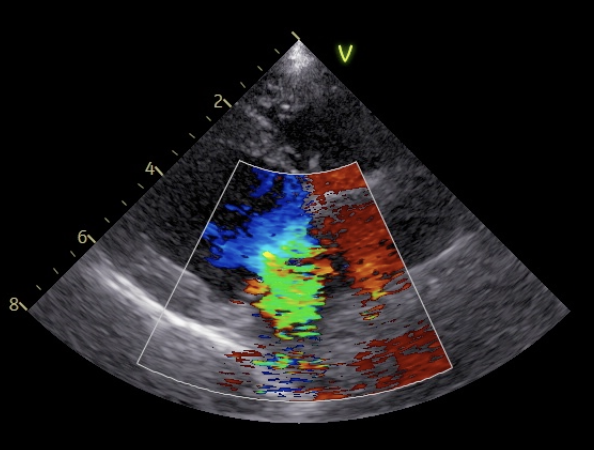

弁輪が縮むことで、僧帽弁の接合する面積が増え、逆流が減ります。

心臓の手術がうまく行くと、僧帽弁逆流はほとんどなくなり、心拡大は良化し苦しかった肺水腫の症状は消失します。逆流がほとんどなくなった場合にはこれまで飲んでいた沢山の薬は必要なくなる場合が多いです。(100%ではございません。)